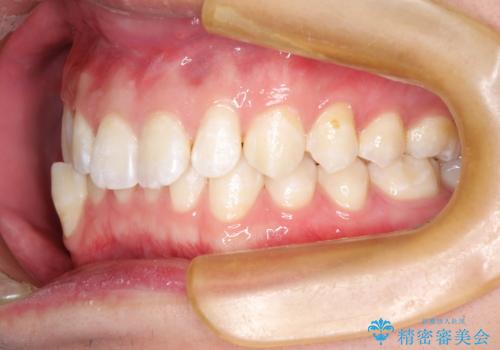

前歯がガタガタ インビザラインによる矯正

- 1年8ヶ月

使用時間を守っていただけたので、比較的スムーズに矯正を終了することができました。